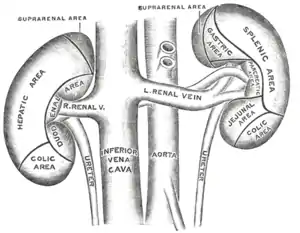

Arteria esplénica

Se origina en el tronco celiaco frente a la 1.ª vértebra lumbar, por lo tanto, lejos del bazo. Después de un corte segmento suprapancreatico, oblicuo hacia abajo y a la izquierda, transcurre transversalmente, sigue el borde superior del páncreas, pasa por delante de la cola u por último llega al hilio del bazo, donde se divide en dos ramas terminales. En sus relaciones del segmento suprapancreático, esta arteria pertenece en ese momento a la región celiaca, esta arteria se encuentra hundida en el plexo celiaco y sus ramos. Está situada detrás del peritoneo parietal, detrás de la porción retrogastrica de la transcavidad de los epiplones que la separa de la parte media de la curvatura menor del estómago. En el segmento retropancreático es cóncava hacia tras como el propio páncreas. Este segmento de la arteria esplénica es muy sinuoso, la arteria aquí comparte sus relaciones con el cuerpo del páncreas: anterior con la cara posterior del estómago a través de la transcavidad de los epiplones, posterior con la raíz y la celda renal izquierda, por intermedio de la facia retropancreática y de la facia prerrenal. Las partes más inferiores se ubican por detrás del páncreas, debajo de esta arteria esta la vena esplácnica. En su segmento Terminal o hiliar, esta describe una curva cóncava al igual que la cola del páncreas. Esta pasa superior a la cola, la vena queda por debajo de la arteria y estos dos vasos llegan al ligamento pancreaticoesplénico en la parte posterior e izquierda de la transcavidad de los epiplones, detrás del estómago y del hilio del bazo.

En sus ramas colaterales se distinguen:

- Ramas pancreáticas destinadas al cuerpo y a la cola, así como la arteria pancreática dorsal. - Rama gástrica, arteria gástrica posterior: de dirección ascendente, irriga la cara posterior del fondo gástrico, el cardias y la cara posterior del esófago abdominal. - Arteria de la extremidad superior: se origina antes que la arteria llegue al hilio, da de dos a tres ramas al fondo gástrico y llega hasta la extremidad superior del bazo.

Da dos ramas terminales que son la superior y la inferior, la superior se dirige hacia la parte alta del hilio donde da de cuatro a seis ramas, la posterior se dirige al tercio inferior de hilio, esta es la que da lugar a las arterias gástricas cortas y a la arteria epiploica izquierda.